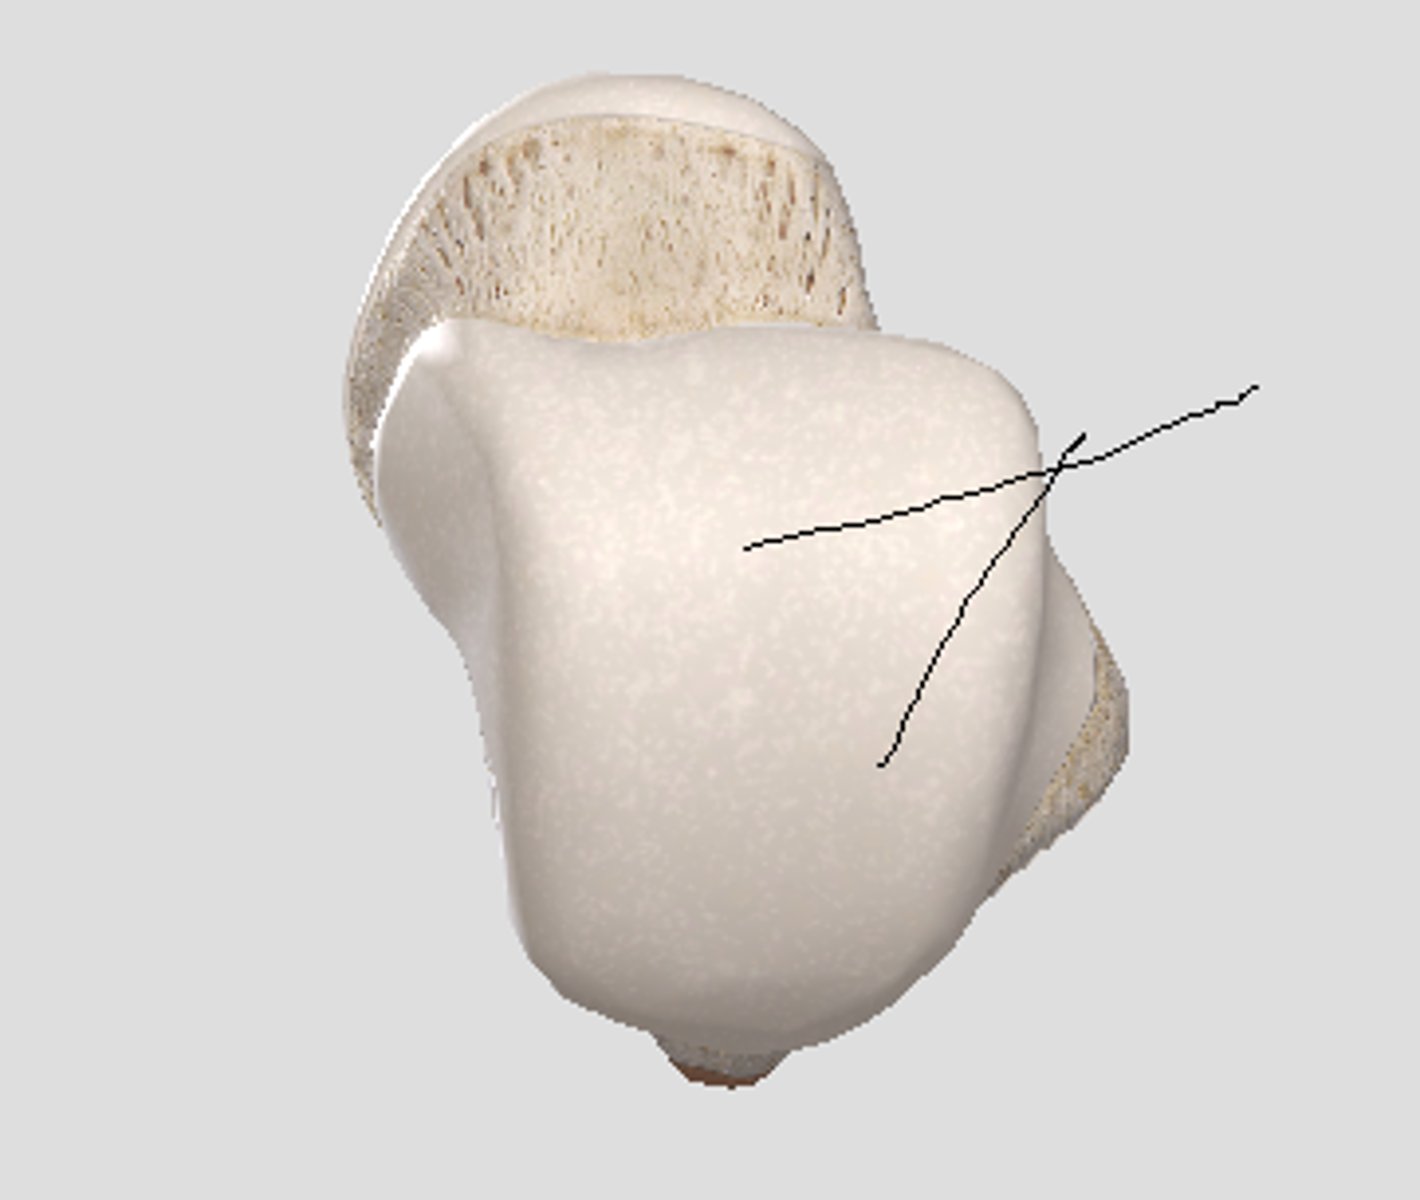

Patella

Apex

inferior surface for patellar ligament

Base

superior surface for quadriceps tendon

Medial articular surface (for medial condyle of femur; smaller)

green

Lateral articular surface (for lateral condyle of femur; bigger)

green